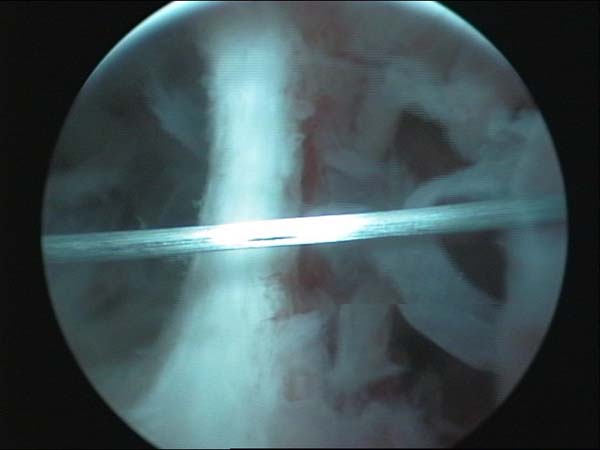

- Hystéroscopie - Hystéroscopie pour l'infertilité

- Clips vidéo de l’hystéroscopie

- Photos de l’hystéroscopie